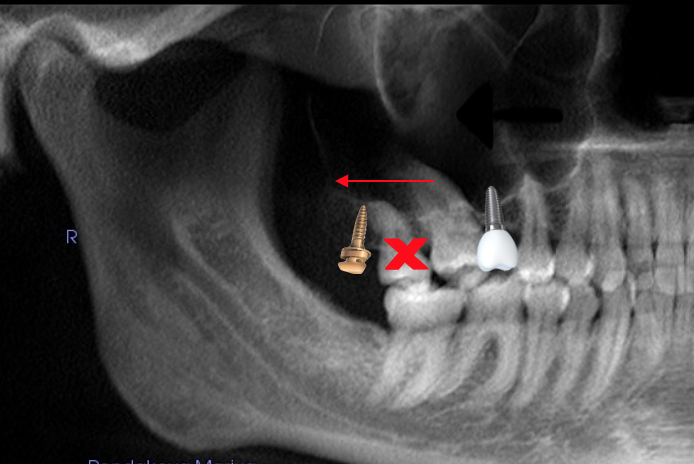

Удаление зуба 1.8 для последующей дистализации и имплантации в области зуба 1.6